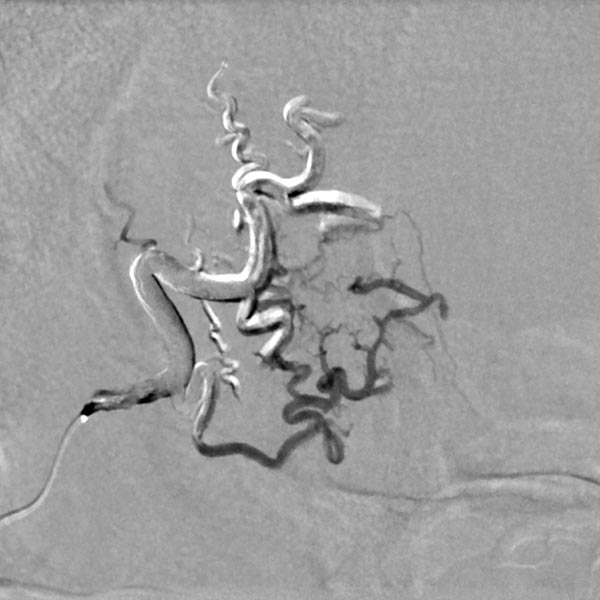

Digital subtraction angiography (DSA) with contrast injection into the right external carotid artery. The superficial temporal artery reveals a microfistulous AVM with markedly dilated feeder arteries on the right forehead with immediate venous outflow.

The microcatheter was advanced directly into the nidus. After visualization of the nidus, immediate direct venous outflow (DSA, venous phase) from the lesion via dilated veins. This confirms the diagnosis of an AVM.

DSA image depicting the arterial inflow, nidus with small arteriovenous fistulae, and venous outflow of the AVM before embolization. The complete angiomorphology of the AVM, at this point untreated, is easily visible.